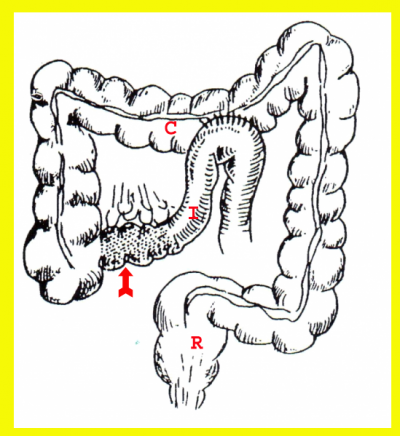

ניתוחים שמרניים אחרים הם: כריתות מוגבלות של הקטעים הנגועים במעי הדק בחולים שיש בהם נגעים מרובים במעי הדק (Skip lesions), שהמרחק ביניהם הוא פחות מ-10 ס"מ. מומלץ לכרות את כל הקטע הנגוע, ואולם אם המרחק גדול יותר, מומלץ להשאיר את הקטע "הבריא" שבין הנגעים ולחבר את הקטעים שנותרו (איור 3.4). בחולים עם היצרויות בקטעים קצרים אפשר לבצע Strictureplasty.